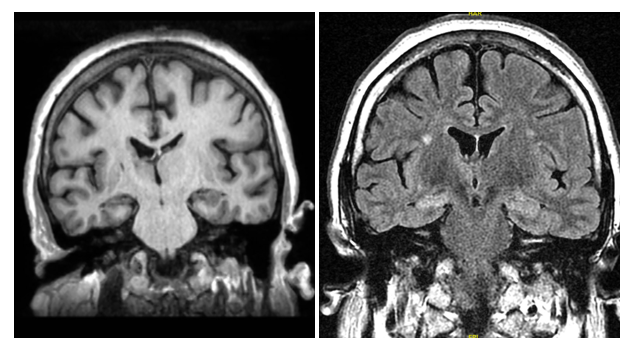

50 yo man w/epilepsy since age 2. Seizures consist of feeling of confusion lasting 2-3 minutes followed by a headache. The seizures are sometimes triggered by stress or excitement & occur monthly. Now with different seizures with sudden collapse and shaking x 2m.

PMH: HTN and epilepsy. SH: No T/E/D. FH: no epilepsy. Meds: lisinopril, topiramate 75 mg, carbamazepine 1200 mg, zonisamide 400 mg, phenytoin 300 mg. No prior records or test results are available.

Examination normal. 30 minute EEG awake and drowsy is normal

MRI brain shown